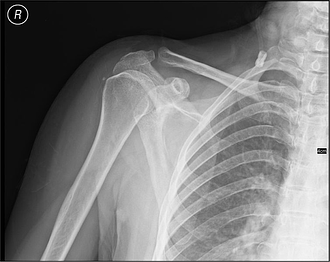

(X-ray image courtesy of Wikimedia)